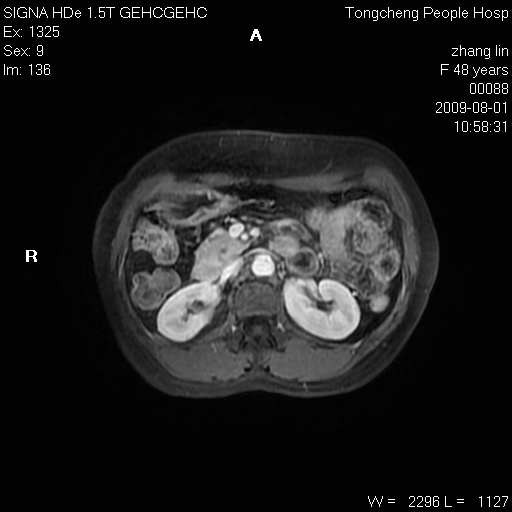

女,48岁。健康体检,彩超发现右肾占位性病变。平素健康。

临床诊断:右肾占位性病变,性质待定(囊肿?肿瘤?)。

上中腹部mr平扫+增强扫描,图像如下:

右肾上极见一类圆形病灶,t1wi呈等信号t2wi呈等高混杂信号,三期增强无强化,边界清---考虑囊肿出血。

同反相位均表现为等信号,病变无强化,考虑含蛋白的囊肿可能,弥散加权相或许有些帮助,

慢性胆囊炎